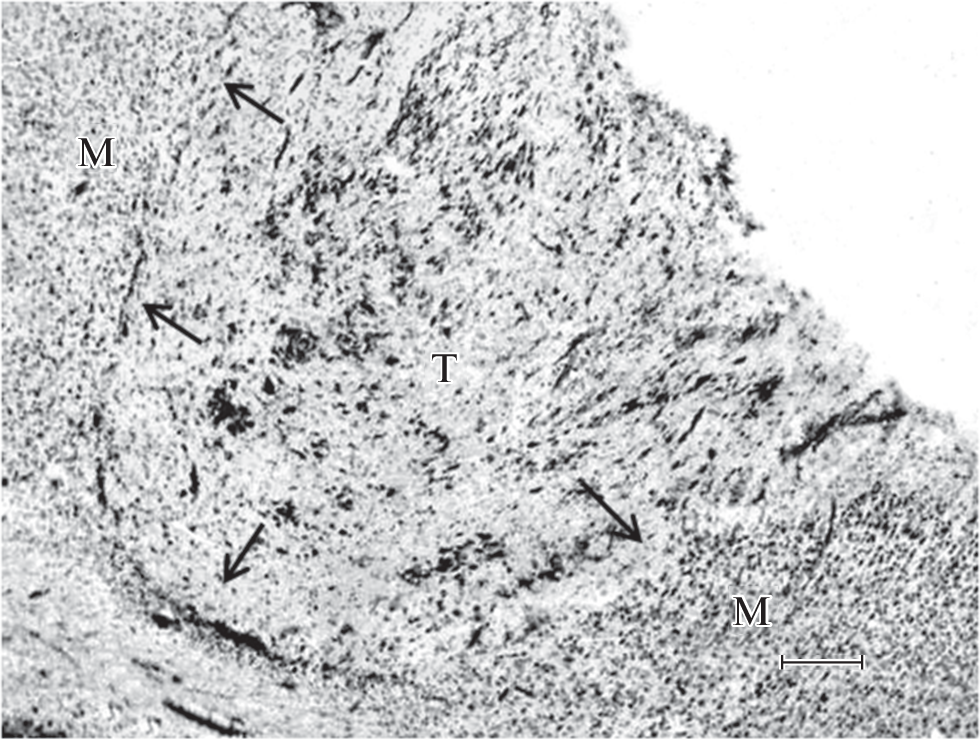

Gamma aminobutyric acid (GABA) plays an important role in regulating the development and functioning of the brain. The aim of this work was to study the involvement of GABA contained in non-neuronal cells in the differentiation and maturation of rat neocortical grafts. Pieces of fetal somatosensory neocortex were transplanted into the acute cavity of the homotopic region of the cortex of adult male rats. 4 months after the operation, the histological and electron microscopic examinations of the grafts were performed. The grafts were well vascularized and consisted of neuronal and glial cells. The localization of GABA in non-neuronal cells was studied by an ultrastructural immunocytochemistry using antibodies conjugated with colloidal gold. The highest expression of immunolabels in the form of electron-dense globules ranging in size from 20 to 60–80 nm was found in protoplasmic astrocytes and their processes. The pericapillary astrocytic endfeets also contained GABA-positive granules. In addition, GABA-positive granules have been observed in some myelin-forming cells and in the endothelial wall of blood vessels. The results obtained showed that GABAergic signaling via non-neuronal cells is involved in the morphofunctional differentiation of the transplanted neocortical tissue.